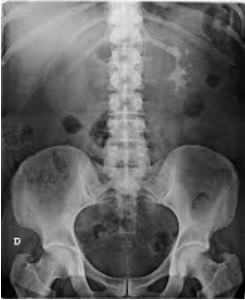

Paciente do sexo masculino, 41 anos, admitido na emergência com dor lombar à E, súbita, de forte intensidade, há 1 hora da admissão. Rx de abdômen abaixo:

Enunciado 747610-1

A composição do achado radiológico é